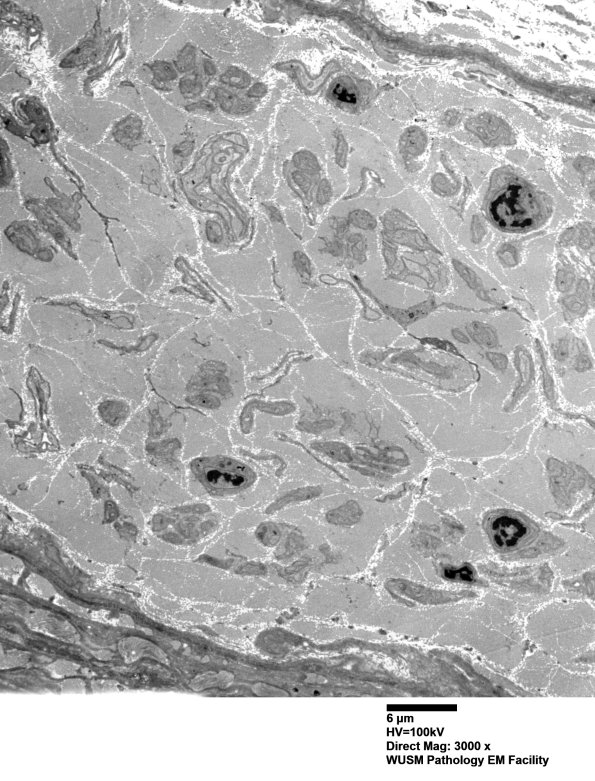

Washington University Experience | PERIPHERAL NEUROPATHY | 4 AXONAL DEGENERATION | 3 Electron Microscopy | 7A1 Chronic Degeneration (Case 33) Sural_058 - Copy

This patient (Case 33) is a 60 year old man with poorly controlled diabetes and established severe sensory neuropathy of more than 10 years duration, often with HbA1c more than 8.0. He has been treated with alpha lipoic acid. ---- 7A1,2 The extensive course of neuropathy in this patient has resulted in the marked increase in endoneurial collagen, loss of many typical bands of Büngner and the proliferation of delicate, questionably atrophic cellular processes (arrows, 7A2). The atrophic processes likely reflect remote bands of Büngner and/or delicate fibroblast processes which may be difficult to separate even with ultrastructural examination. (electron micrographs)